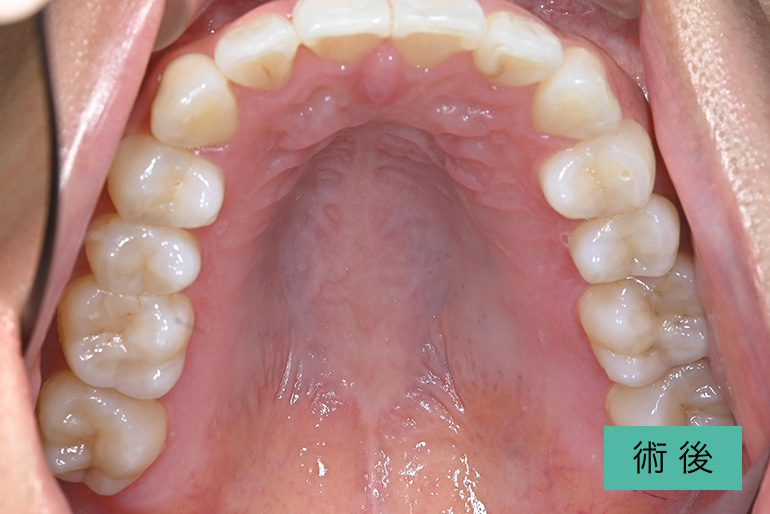

オールセラミック①

| 治療内容 | 上顎インビザライン矯正 右上1番から左上の2番のセラミック冠 上顎前歯の叢生、右上犬歯の捻転の改善のため、上顎のみインビザライン矯正を行なった また、根尖病巣があった為補綴を除去、顕微鏡根管治療を行い、セラミック冠を装着した |

| 治療期間・回数 | 約8ヶ月、15回(インビザライン矯正) 約4ヶ月、6回(補綴治療) |

| 費用(税込) | ¥275,000 (上顎インビザライン矯正) ¥495,000(165,000/1本)(補綴費用) ※自由診療 |

| リスク・副作用 | 疼痛、補綴物の脱落、咬合違和感、破折 |